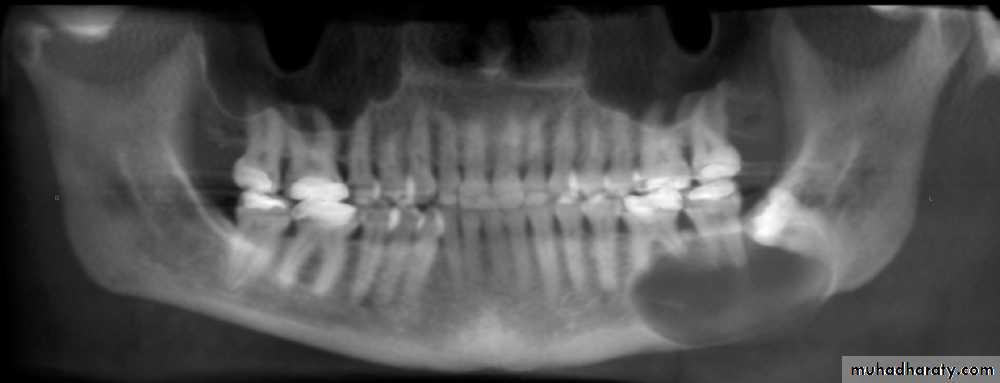

Most lesions are discovered on routine radiographic examination.A well-defined radiolucency of bone apical to the offending tooth. Loss of the apical lamina dura.

The lesion may be circumscribed or ill defined.

The size is variable.

in most cases is identical to periapical granuloma,but, the cyst may be of greater size than the granuloma.Occasionally the apical periodontal cyst exhibits a thin, radiopaque line around the periphery of the radiolucent area, and this indicates a reaction of the bone to the slowly expanding mass.